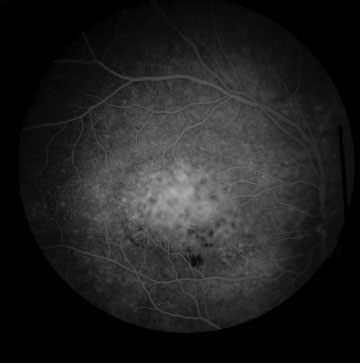

Optical coherence tomography, OCT, (sjónhimnusneiðmynd) sýndi vessandi sjónhimnulos (mynd 1A). Augnbotnamynd sýndi sorturek í makúlu (mynd 2A) og fluorescein æðamynd af augnbotni (mynd 3) sýndi vel afmarkað æðahimnuæxli á miðhluta makúlu.

Mynd 3. Fluorescein æðamynd fyrir meðferð sýnir vel afmarkað æðahimnuæxli á miðhluta makúlu.